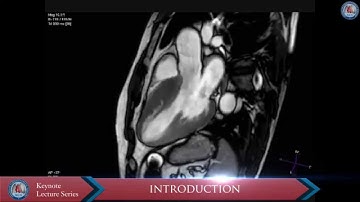

POST MYECTOMY VSD CLOSURE WITH PMVSD DEVICE IN HYPERTROPHIC OBSTRUCTIVE CARDIOMYOPATHY